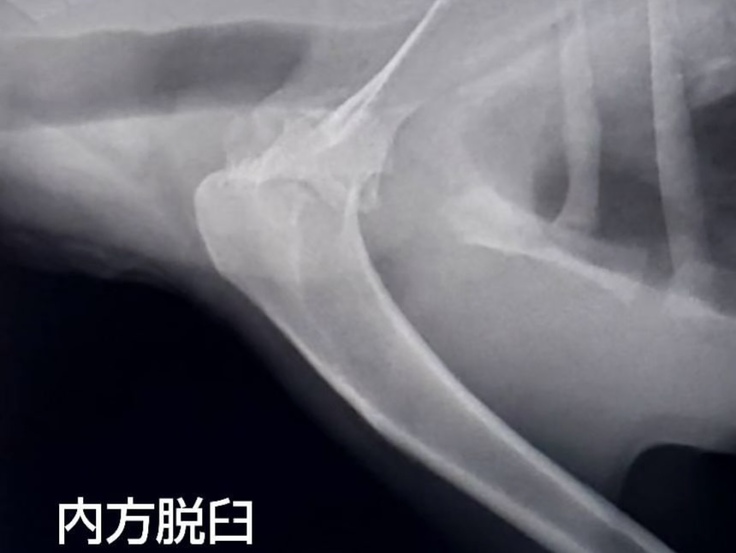

ただ、右の前足を地面につけずに歩き、角度も少し通常とは違う。何人かの獣医さんに相談し、出た診断は「肩の内方脱臼」。

手術でプレート固定を勧められました。回復率は85%程度。費用はいくらかかるんだろう。でも、やってみて良くなる可能性があるのであれば、手術をしていただこう、という決断になりました。

(この後、レントゲン写真や術後の患部の写真があります。苦手な方は避けてください)